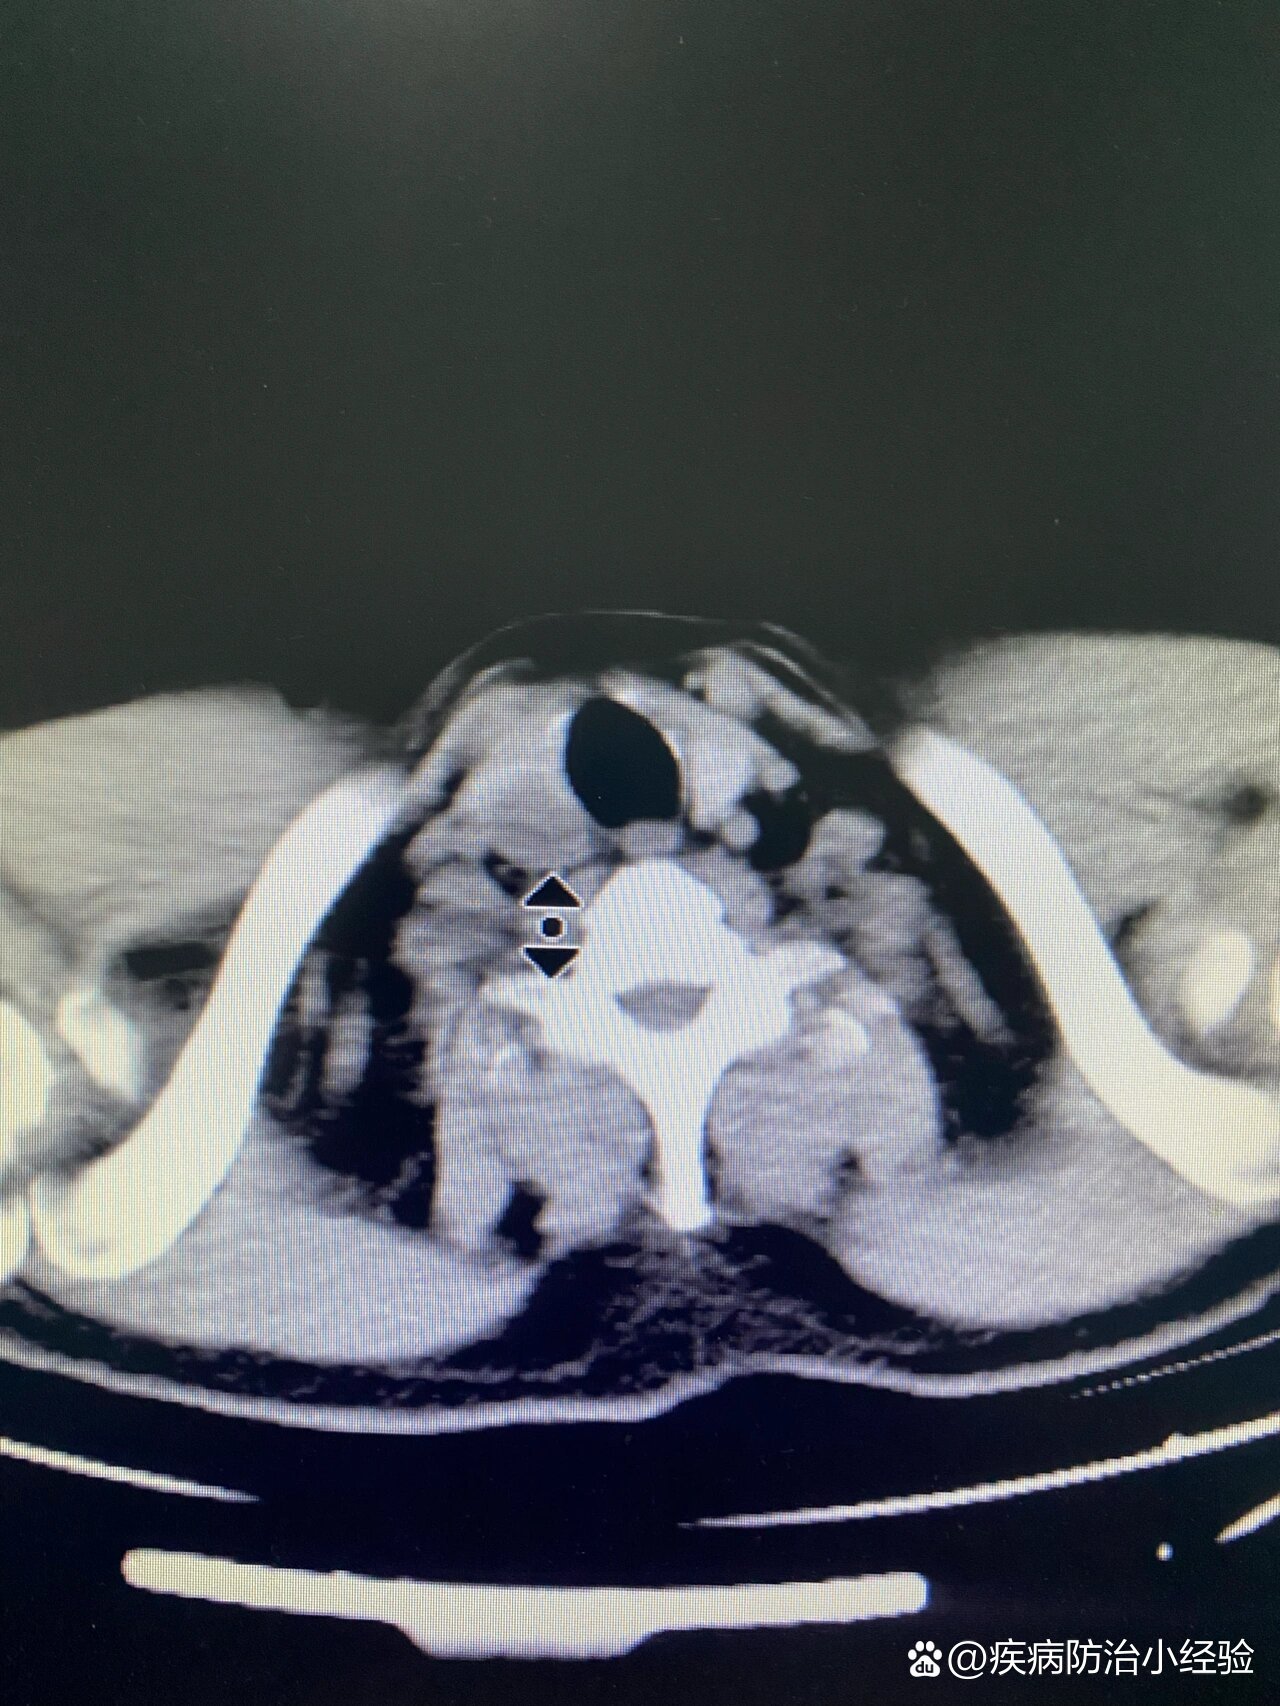

【讨论】甲状腺病变(三)【伪影太强,此贴只能用来讨论扫描技术方面的

少见病例,大家看看象啥.(已经公布病理: 胸内甲状腺肿)